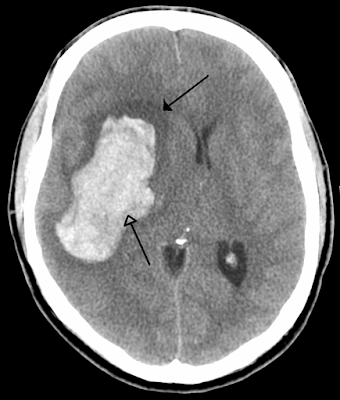

In animal models of ICH and human imaging studies there is a zone of hypoperfusion surrounding a clot. So the questions is, will rapid reduction of BP in ICH result in infarction around the area of hemorrhage? There have been several studies which have looked at this question.

ICH ADAPT:

The ICH ADAPT study was a multi-centre, prospective, randomized, open-label, with blinded evaluation study. One of the authors was Dr. Dowlatshahi one of our stroke neurologist here at the The Ottawa Hospital who has a special interest in ICH. We will get to some of his recommendations later on.

In this study eligible patients were those with spontaneous ICH diagnosed on CT < 24 hours after onset with SBP ≥150 mm Hg. Patients with evidence of secondary ICH (eg, vascular malformation), planned surgical resection, or contraindications to CT perfusion were excluded.

Their hypothesis was that early acute BP reduction would not result in significantly lower peri-hematoma CBF compared to patients managed conservatively.

Their primary outcome was to look at CBF in the peri-hematomal region using CT-perfusion scans in an aggressively treated vs non aggressively treated group. They looked at secondary end points of clinical outcomes and ICH expansion but this was a small study and was not powered to detect any differences

This study essentially showed no difference in perihematomal CBF. There was no statistical difference in clinical outcomes or ICH size increase which is maybe not surprising given their small numbers.

This study supported that rapid lowering of BP in ICH is likely safe and we needed more trials to figure out if it might be helpful.